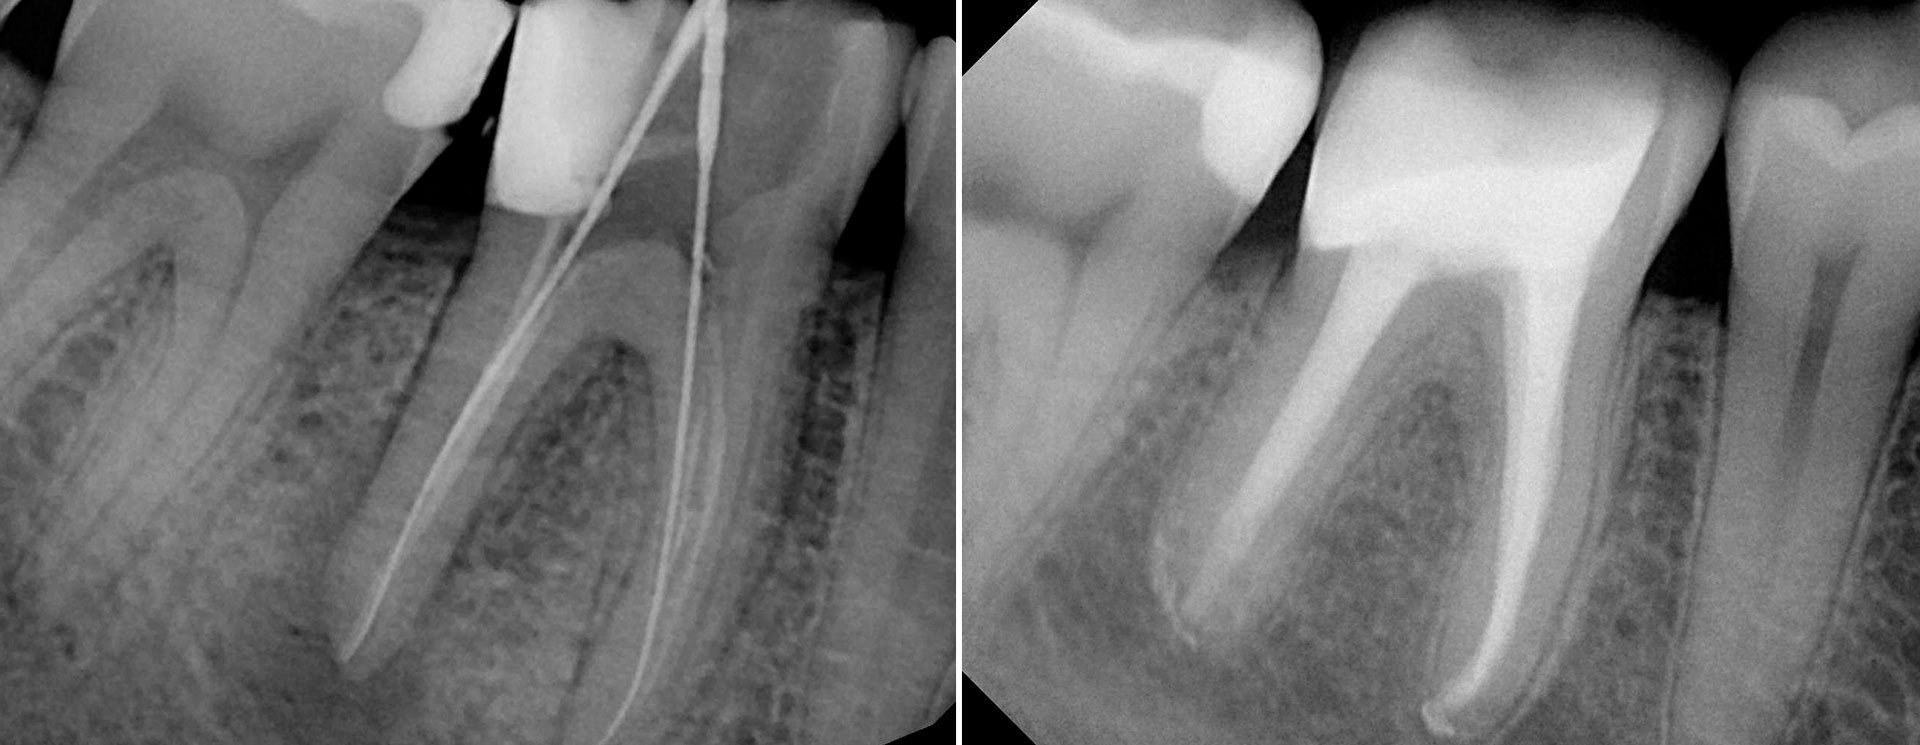

A Endodontia é a área da Medicina Dentária que envolve o “tratamento” dos tecidos no interior e em redor dos dentes. O tratamento endodôntico, mais conhecido como desvitalização, consiste na eliminação da polpa dentária (“nervo” do dente) e desinfeção do interior do dente, seguida do preenchimento e selamento das raízes com um material biocompatível.

O tratamento endodôntico é necessário dado que existem vários fatores que podemprovocar patologia pulpar: cáries de grandes dimensões, restaurações infiltradas profundas, desgastes dentários acentuados com exposição de dentina e lesões traumáticas. Na maioria destes casos existe sintomatologia associada à inflamação dos tecidos em redor do dente e que envolve dor constante e forte a estímulos térmicos (frio/quente), dor à mastigação e, em casos mais avançados, edema facial.

É importante sublevar que o tratamento endodôntico é um tratamento limite e que, por vezes, é a única forma de eliminar infeções dentárias e evitar a extração do dente. Como o dente é formado por tecidos duros e é uma estrutura fechada rodeada por tecidos duros (osso), só a abertura do dente e sua limpeza e desinfeção é capaz de eliminar os agentes patogénicos responsáveis pela inflamação/infeção.